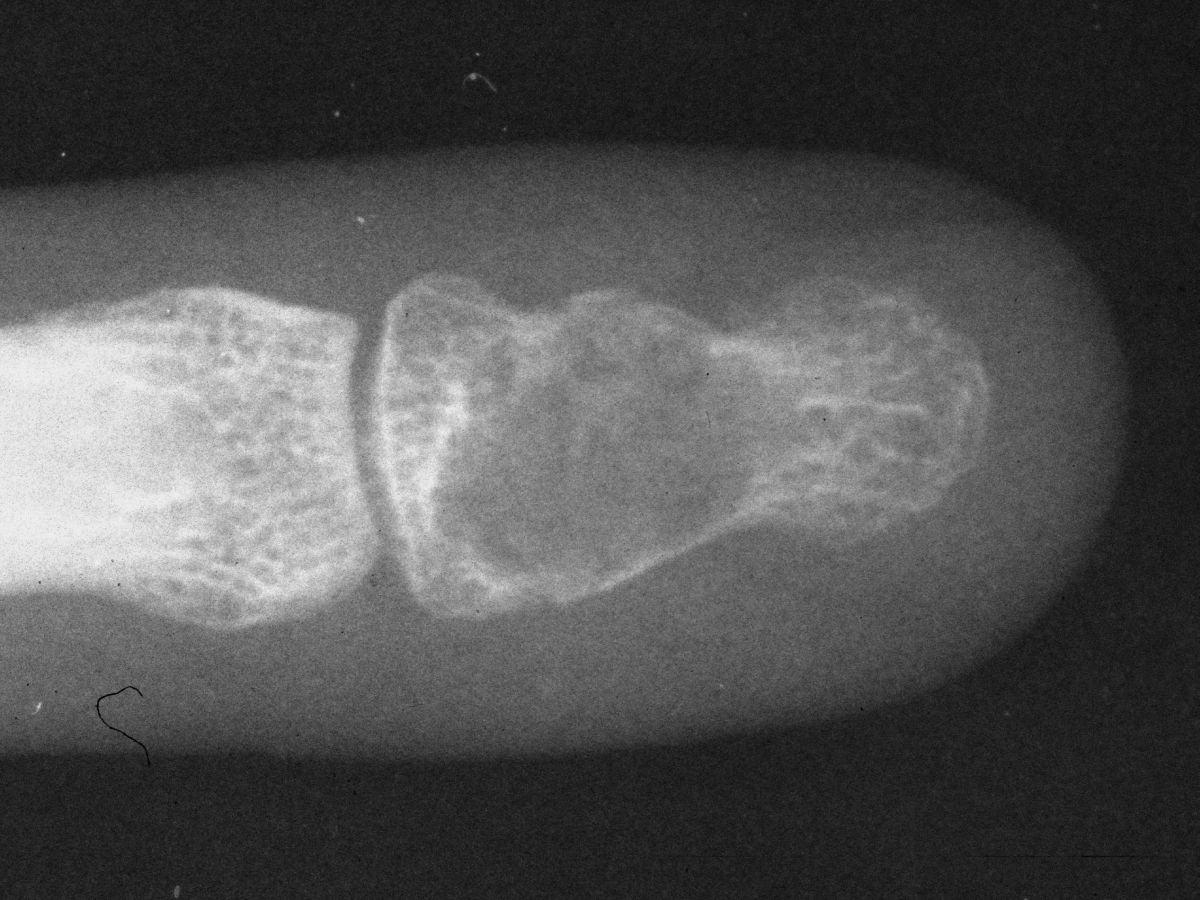

| Case 1. This patient presented with pain with thumb pinch and a sense of fullness in the thumb pulp. Plain radiographs demonstrate an expansile, geographic, radiolucent, juxtaarticular intraosseous mass, typical for an enchondroma. There is circumferential cortical thinning and possible cortical breaks. |